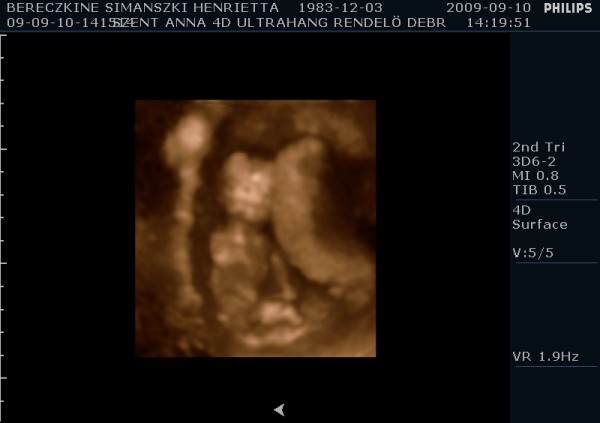

Megjöttem én is ismét, tettem fel képeket. A párom ragaszkodott hozzá, hogy kérjünk DVD-t, így hát átkapcsoltak 4D-be is. Kb. 10-15 perc lett a dvd, nagyon jópofa, látszik mindene. Mozognom, köhögnöm kellett nekem is, hogy a baba felébredjen, de amikor ébren volt, hihetetlen mit művelt. Egyik helyről a másikra átment, az első képen épp ez látható. :-) Ott a lábai vannak alul, a térdei nagyon jól látszanak. Épp ekkor rúgta át magát egy neki kényelmesebb pozícióba. :-)

Ami még érdekes, hogy tegnap 49mm-nek mérték, ma pedig 55mm-nek a CRL-t. A nyaki redő tegnap 1,4mm volt, ma az 1,3mm lett, itt nem nagy a különbség.